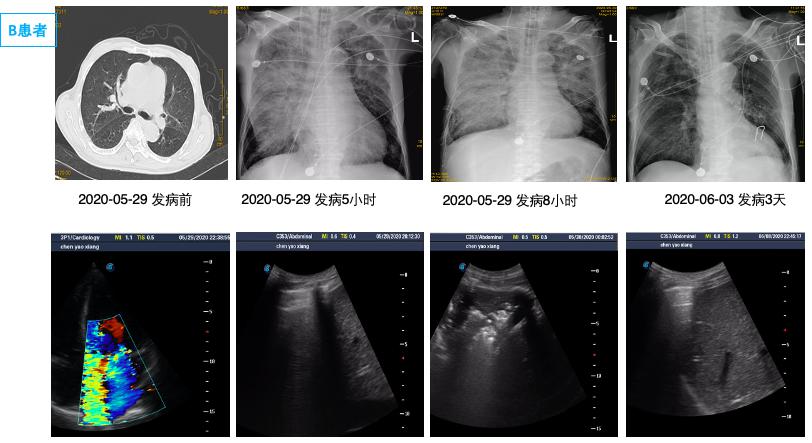

1.3 病例分组根据影像学表现分为双侧PE组和单侧PE组。单侧PE包括右侧和左侧PE(图 1图 2)。

| (A1、A2为同一患者,左侧PE,男,65岁,A1为发病前,A2为心脏骤停4 h后。B1、B2为同一患者,右侧PE,男,68岁,B1为心脏骤停后4 h后,B2为治疗3 d后。) 图 1 单侧肺水肿胸片表现 Fig 1 Manifestations of unilateral PE on X-ray |

2 结果通过病历系统回顾性分析2018年1月至2021年1月,共纳入314例患者,其中男性179例,女性135例,年龄18~97岁[(58.8±16.9)岁]。单侧PE患者共14例,发病率4.5%,男性10例,女性4例; 其中以右侧为主单侧PE 11例(78.5%),左侧PE患者3例(21.5%)。1例单侧PE呈右肺上叶局限性分布,(见图患者C),1例单侧PE以左下肺为主(见图患者A),其余单侧PE分布无明显肺段特点。